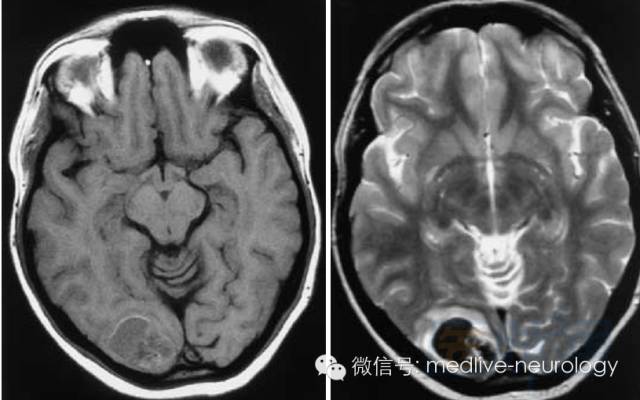

然后解决第三个问题,轻松一下,图来啦,让我们巩固一下今天学习的成果,均为先T1,后T2。

亚急性早期(3-7d): 脑桥

亚急性晚期(7-14d): 左硬膜下